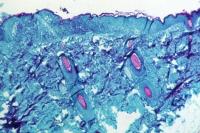

Terkonfirmasi 131 Kasus Cacar Monyet di Luar Afrika, WHO Sebut Bisa Dikendalikan

WHO: Tidak Ada Bukti Bahwa Virus Cacar Monyet Telah Bermutasi.